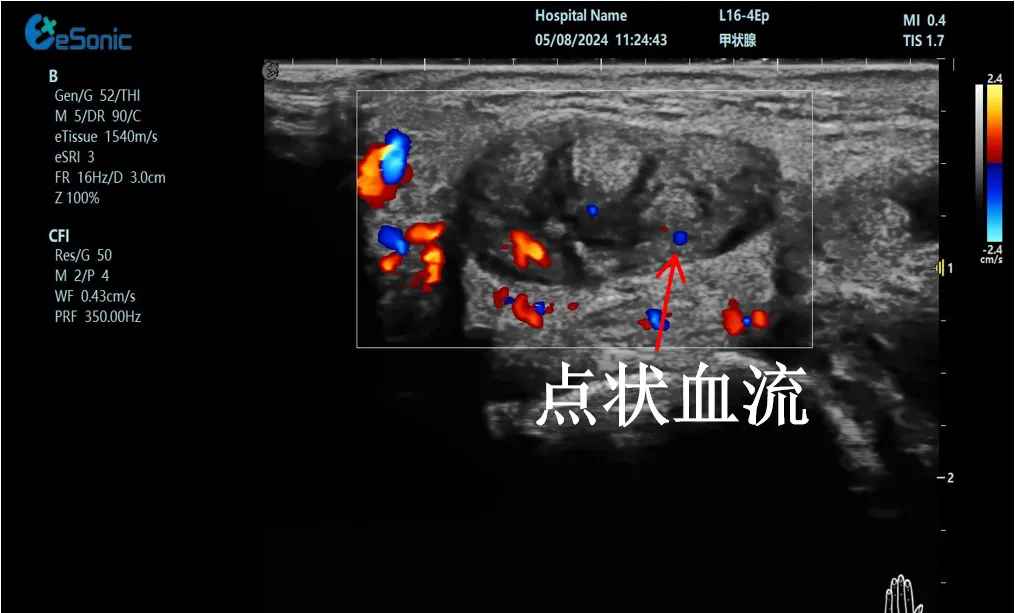

mFlow?技术在腱鞘炎诊疗中的应用

【痛点】:普通彩色多普勒不敏感,只能看到细小点状血流,容易被忽略,难以进行分级诊断和疗效评估。

【方案】:百乐博平台医疗(ESI)超微血流技术可以看到腔室内肌腱周围环状血流,可充分提示:

1、处于炎症活动期;

2、根据血流进行分级诊断提示1级;

3、治疗后根据血流多少评估疗效(见右下图:治疗10天后复查超声,微血流图像血供消失)。